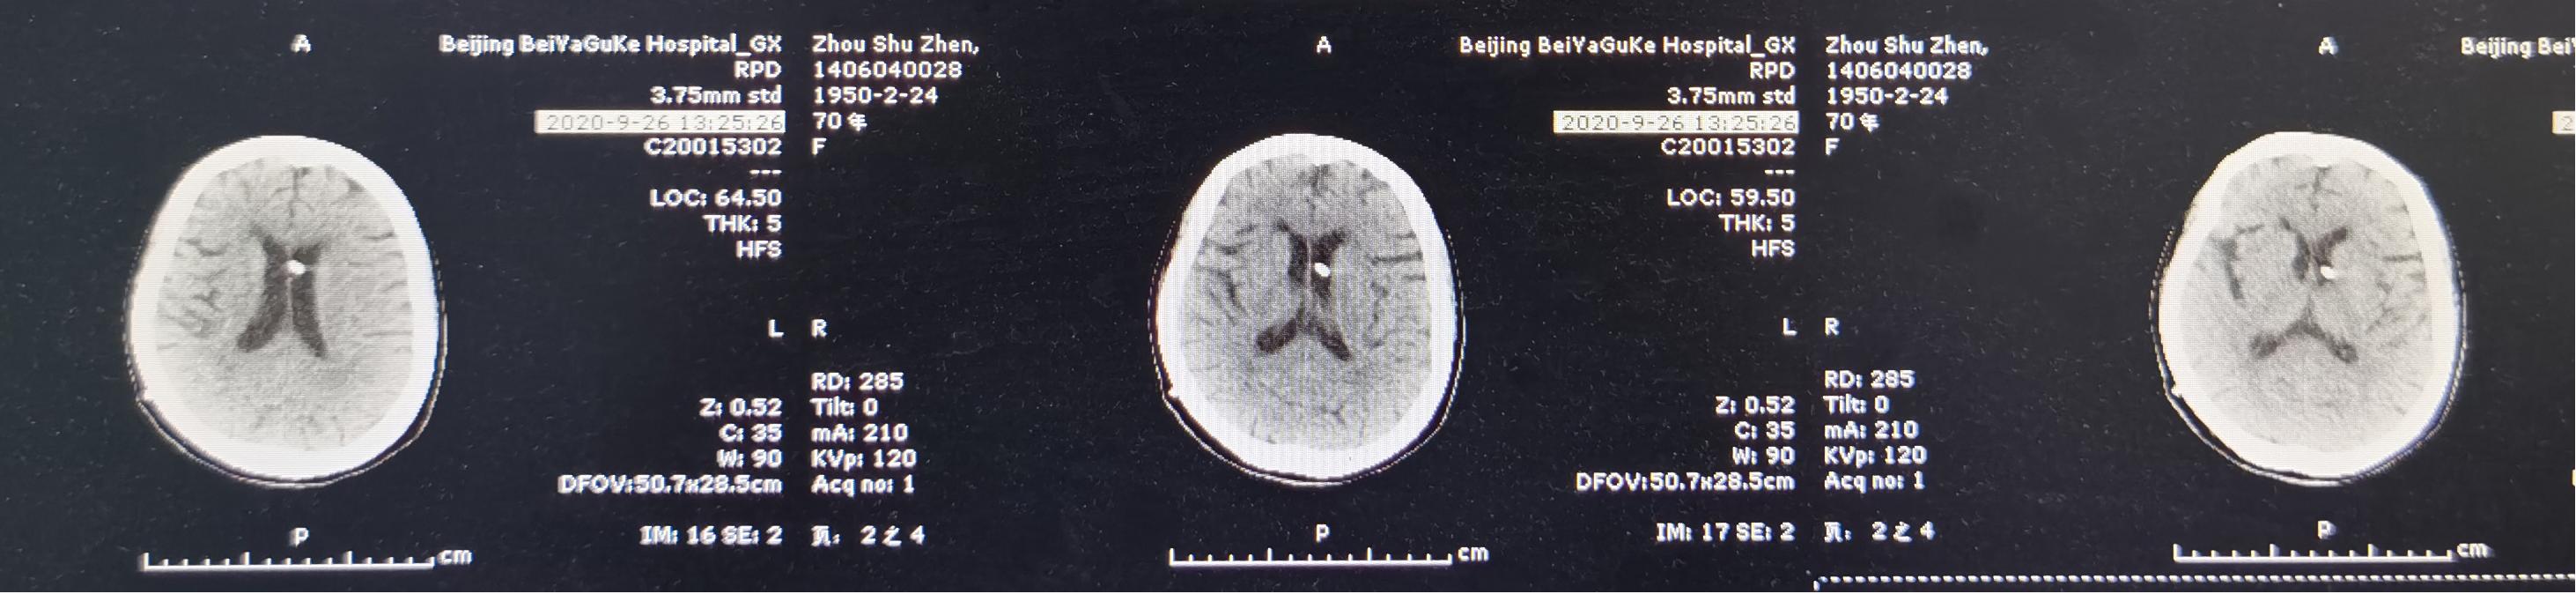

2020年9月26日(入脑脊液科第26天,即脑室外引流术后第23天,即颈椎脑脊液漏修补术后第30天,即第二次颈椎病术后第43天),夹闭引流管后无伤口脑脊液漏,复查头颅CT示脑室无扩张积水( 图-15 )。

图-15: 2020年9月26日头颅CT